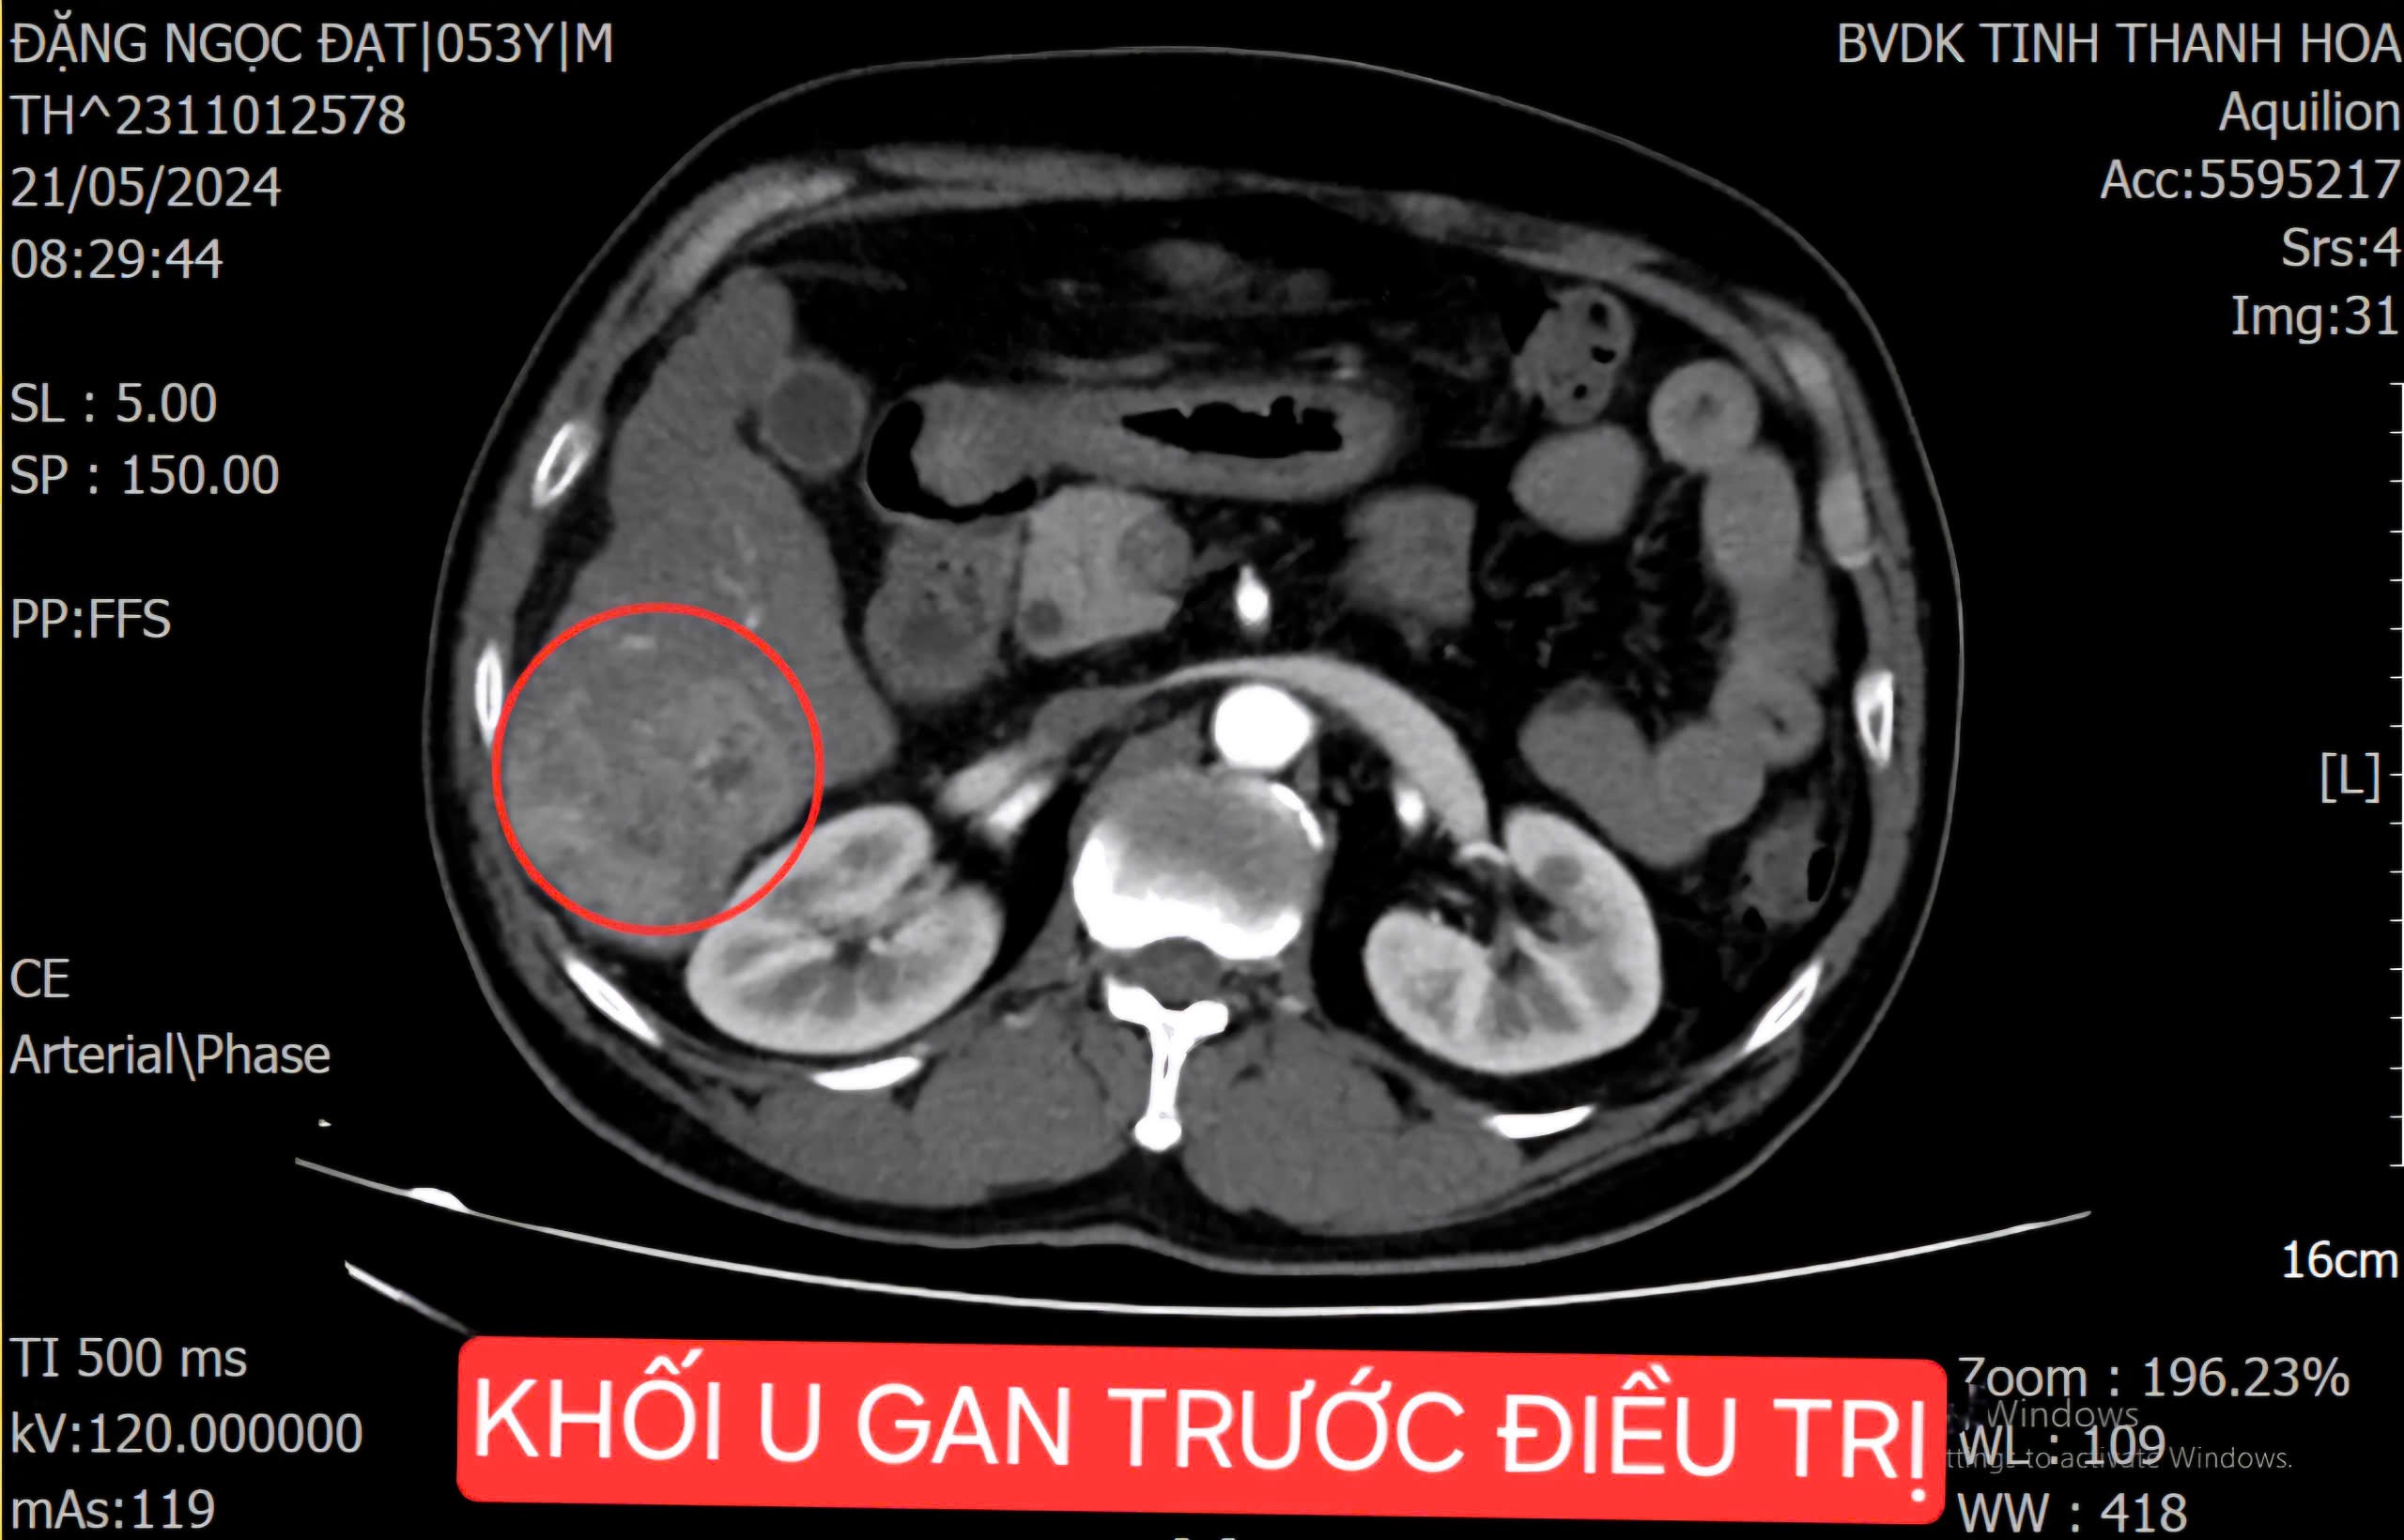

Hình ảnh khối u gan của bệnh nhân trước can thiệp nút mạch

Bệnh nhân Đ.N.Đ (54 tuổi, Đại Lộc, Hậu Lộc) nhập viện trong tình trạng đau vùng hạ sườn phải kéo dài, dù đã điều trị tại các bệnh viện tuyến trung ương nhưng không mang lại hiệu quả. Sau quá trình thăm khám, làm các xét nghiệm chuyên sâu, bệnh nhân được chẩn đoán mắc ung thư biểu mô tế bào gan (HCC) giai đoạn cuối, có huyết khối tĩnh mạch cửa nhánh phải trên nền xơ gan, với khối u có kích thước lên tới 75x34mm.